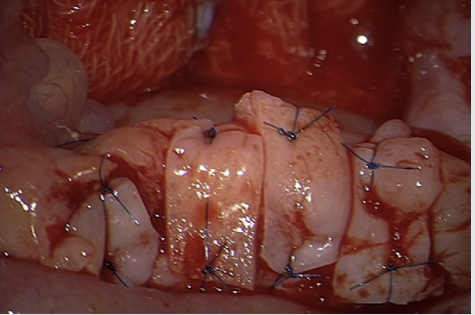

| Hình: Tái cấy ghép mô buồng trứng sau đông lạnh (Donnez, 2013) |